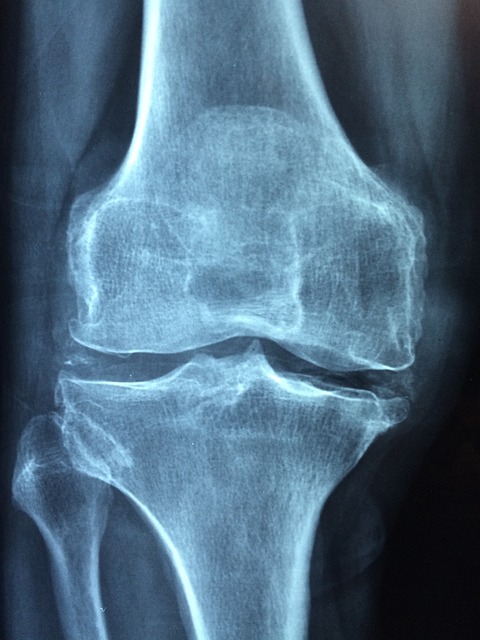

- 대상 질환 : 건강보험급여 '인공관절치환술(슬관절)' 인정기준에 준하는 질환자